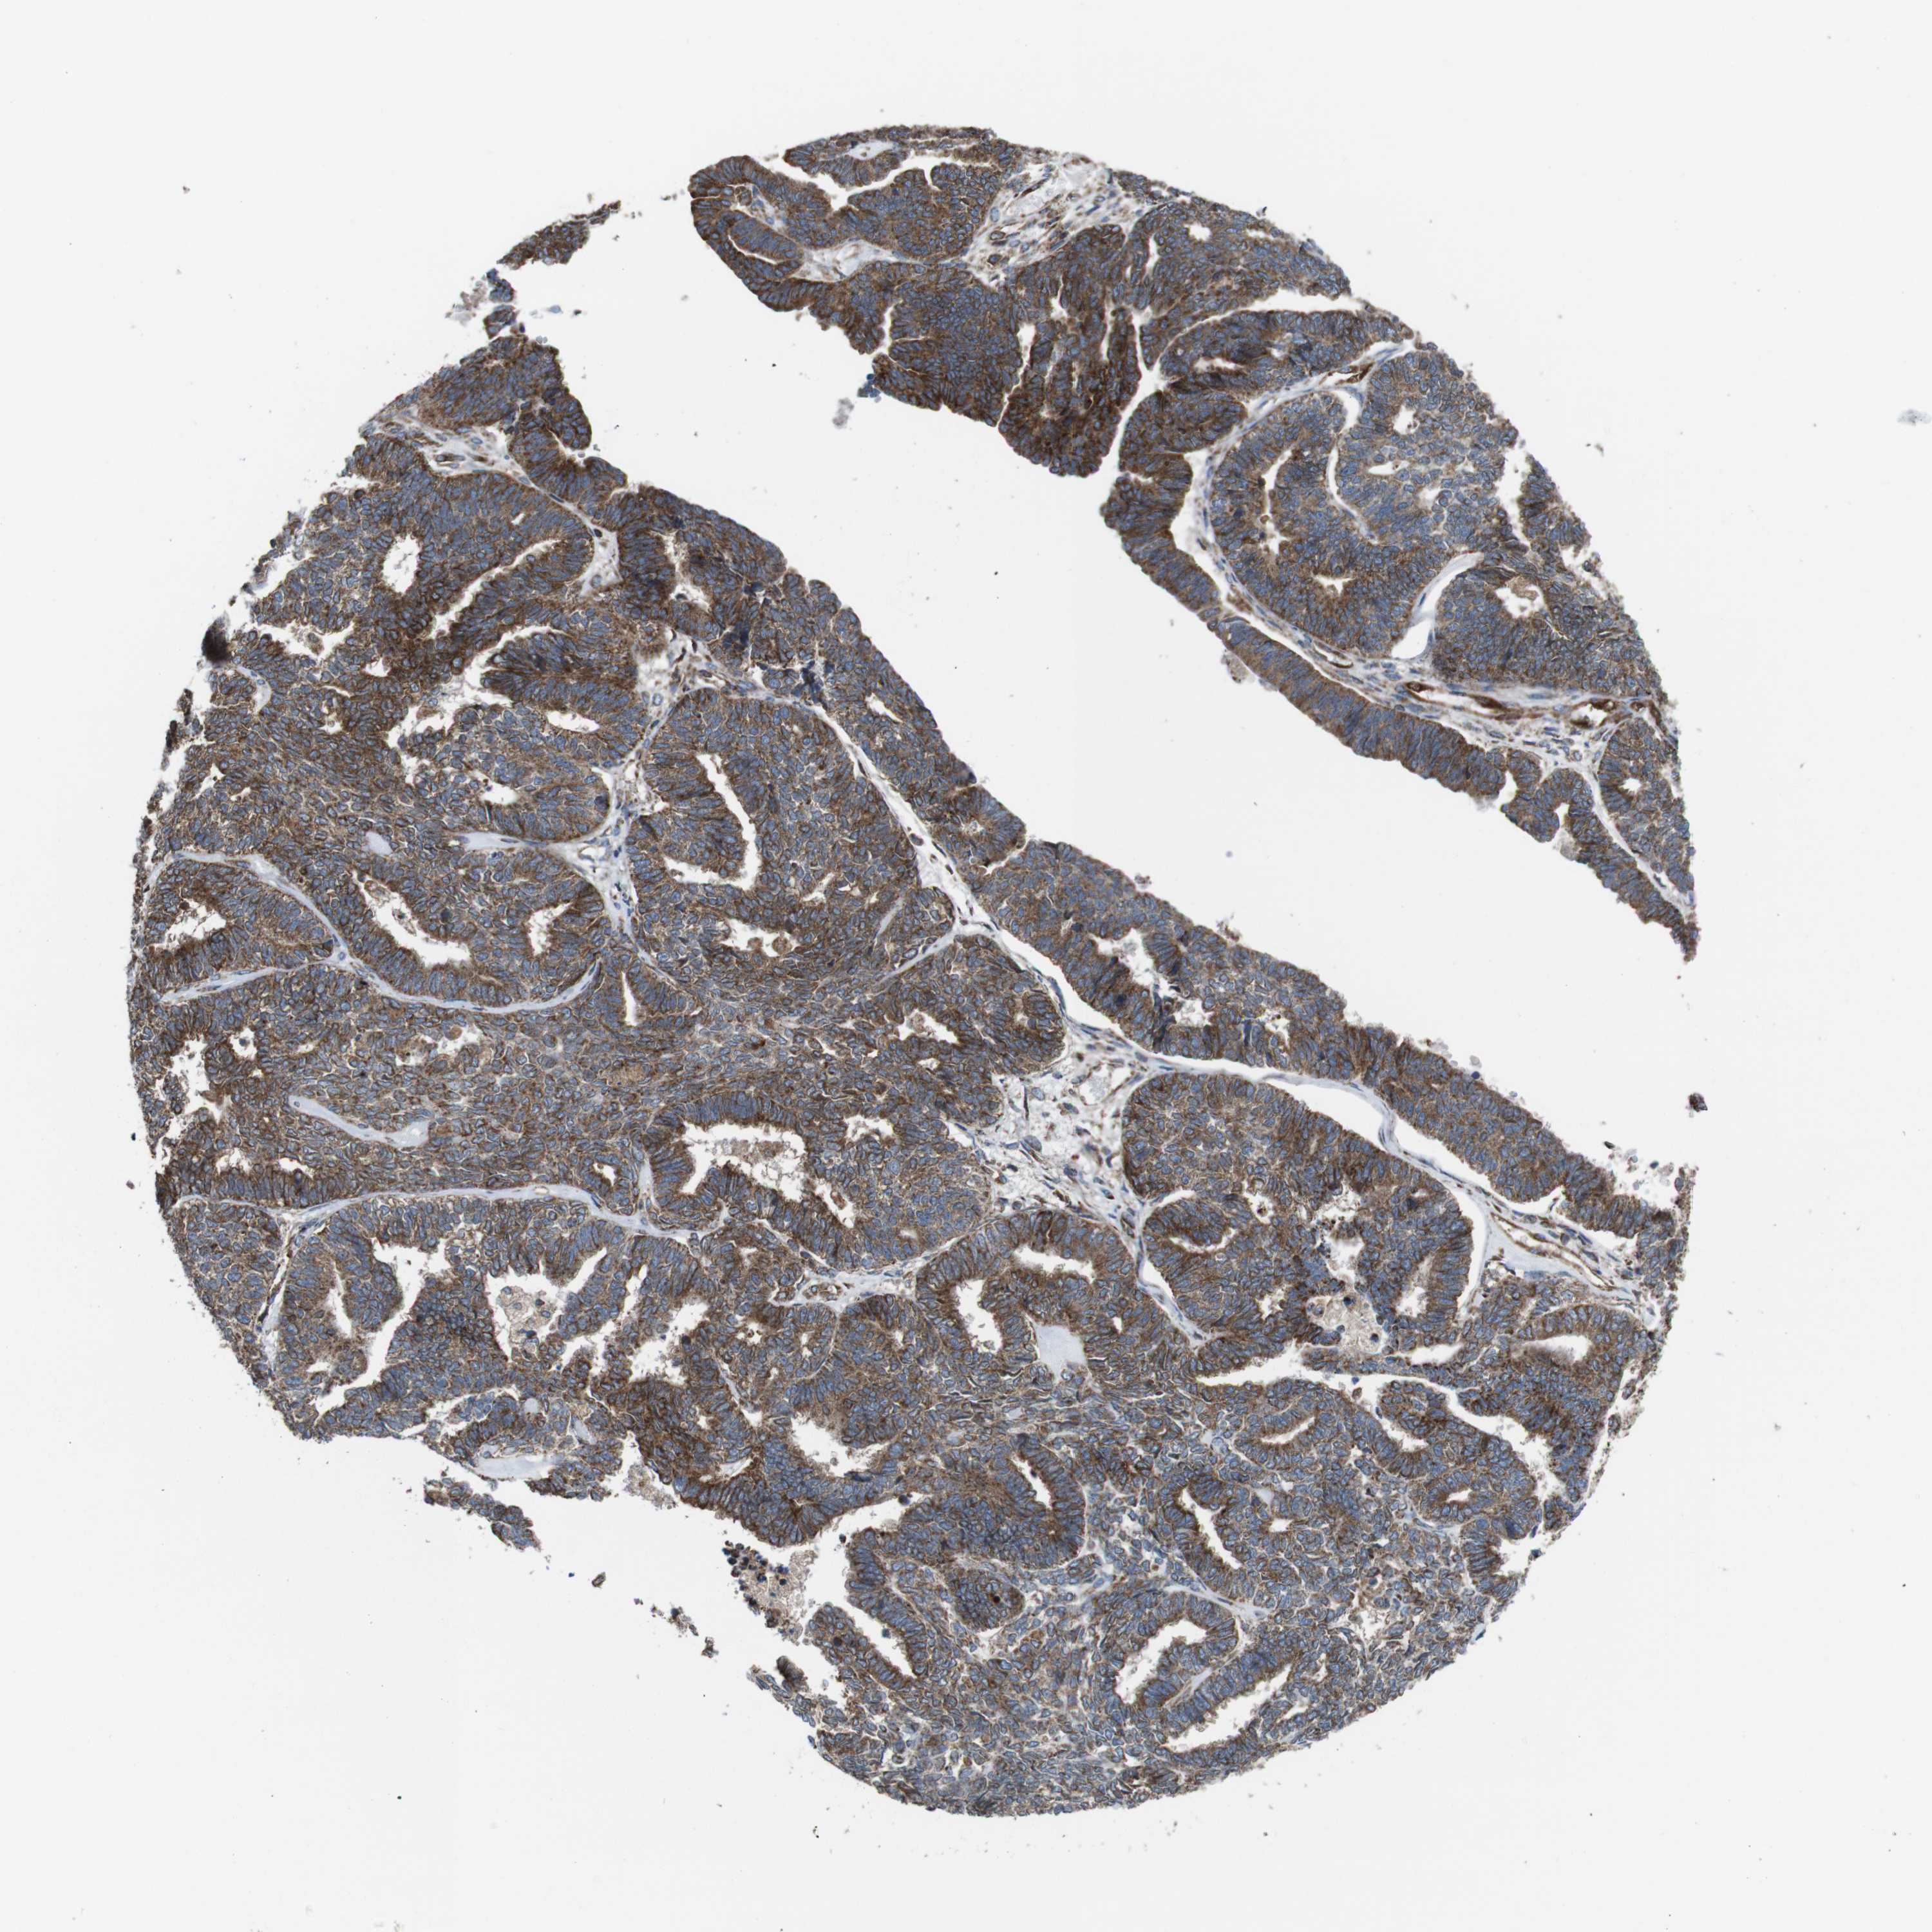

ENDOMETRIAL CANCER - Protein expressioni

A mouse-over function shows sample information and annotation data. Click on an image to view it in a full screen mode. Samples can be filtered based on level of antibody staining by selecting one or several of the following categories: high, medium, low and not detected. The assay and annotation is described here.

Note that samples used for immunohistochemistry by the Human Protein Atlas do not correspond to samples in the TCGA dataset.

Antibody stainingi

Antibody staining in the annotated cell types in the current human tissue is reported as not detected, low, medium, or high, based on conventional immunohistochemistry profiling in selected tissues. This score is based on the combination of the staining intensity and fraction of stained cells.

Each image is clickable and will lead to virtual microscopy that enables deeper exploration of all samples and also displays staining intensity scores, fraction scores and subcellular localization as well as patient and tissue information for each sample.

Antibody HPA007043

Antibody HPA007044

Antibody CAB010052

Staining

High

Medium

Low

Not detected

Intensity

Strong

Moderate

Weak

Negative

Quantity

>75%

75%-25%

<25%

None

Location

Nuclear

Cytoplasmic/membranous

Cytoplasmic/membranous,nuclear

Adenocarcinoma, NOS